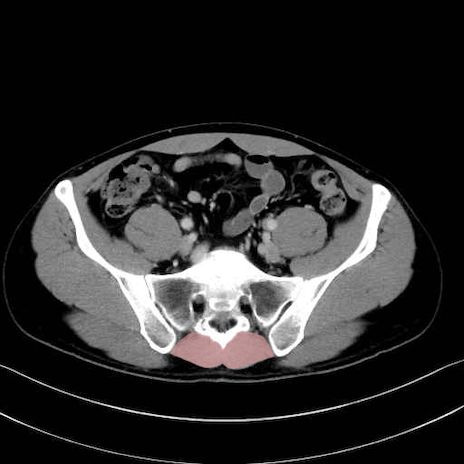

肛門挙筋 (Levator ani)